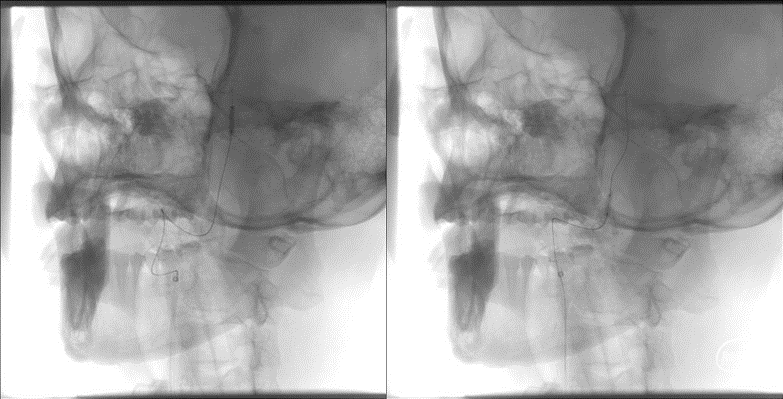

头颅核磁示:双侧小脑、双侧枕叶多发性脑梗死,部分趋于急性期。头颅磁共振MRA提示:双侧椎动脉V4重度狭窄;基底动脉上段轻度狭窄。

手术方案:全麻下行右侧椎动脉V4段血管成形术(Gateway球囊预扩张后置入Neuroform EZ自膨式支架),

300cm微导丝携Gateway球囊到位,行球囊扩张及预扩张后造影。